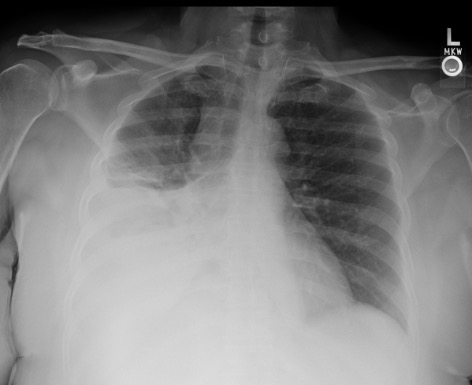

US survey — effusion + pre/post

Pre-procedure ultrasound showing right pleural effusion Pre-procedure CXR showing large left pleural effusion